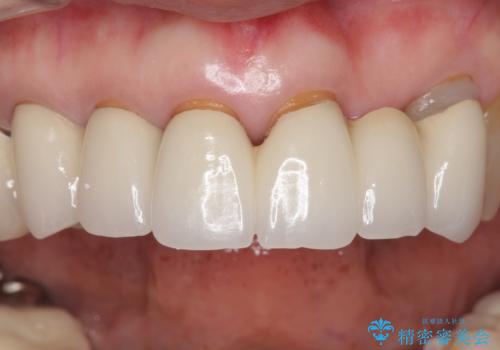

金属を使わないジルコニアセラミッククラウンの自然な仕上がりにご満足頂けました。

また、古い被せ物はブリッジではない右上321も連結されていましたが、1本1本の歯の動揺がなく連結する必要がないと判断し単冠による補綴を行いました。

単冠の部位は天然歯のようにフロスを通すことができるため、セルフメンテナンスもしやすくなったと患者様に喜んで頂けました。

被せ物の種類:ジルコニアセラミッククラウン スタンダード